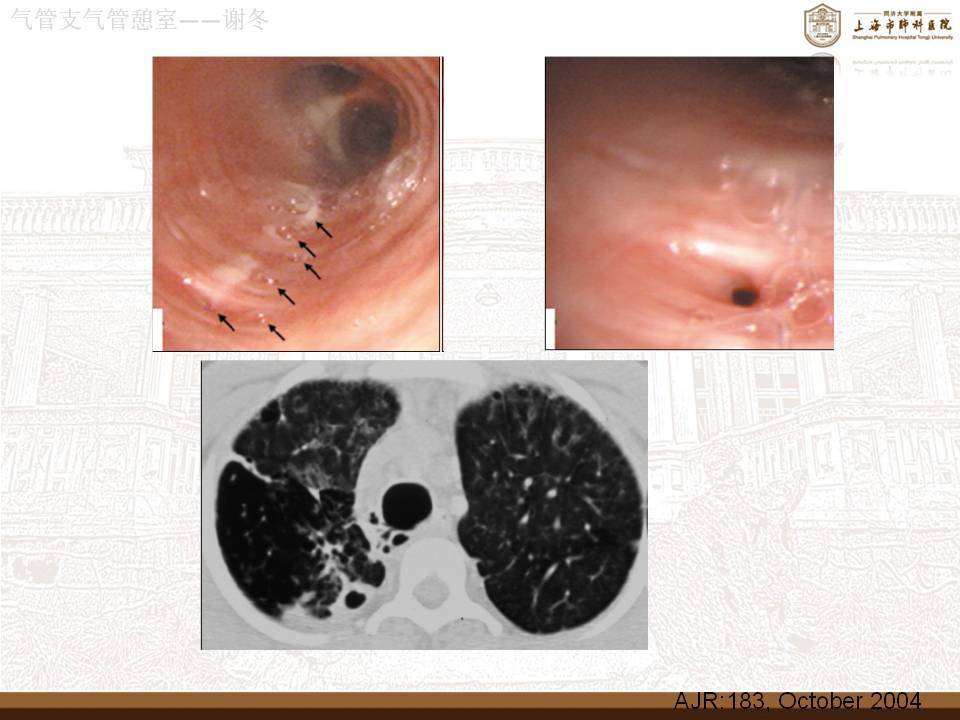

气管,支气管憩室